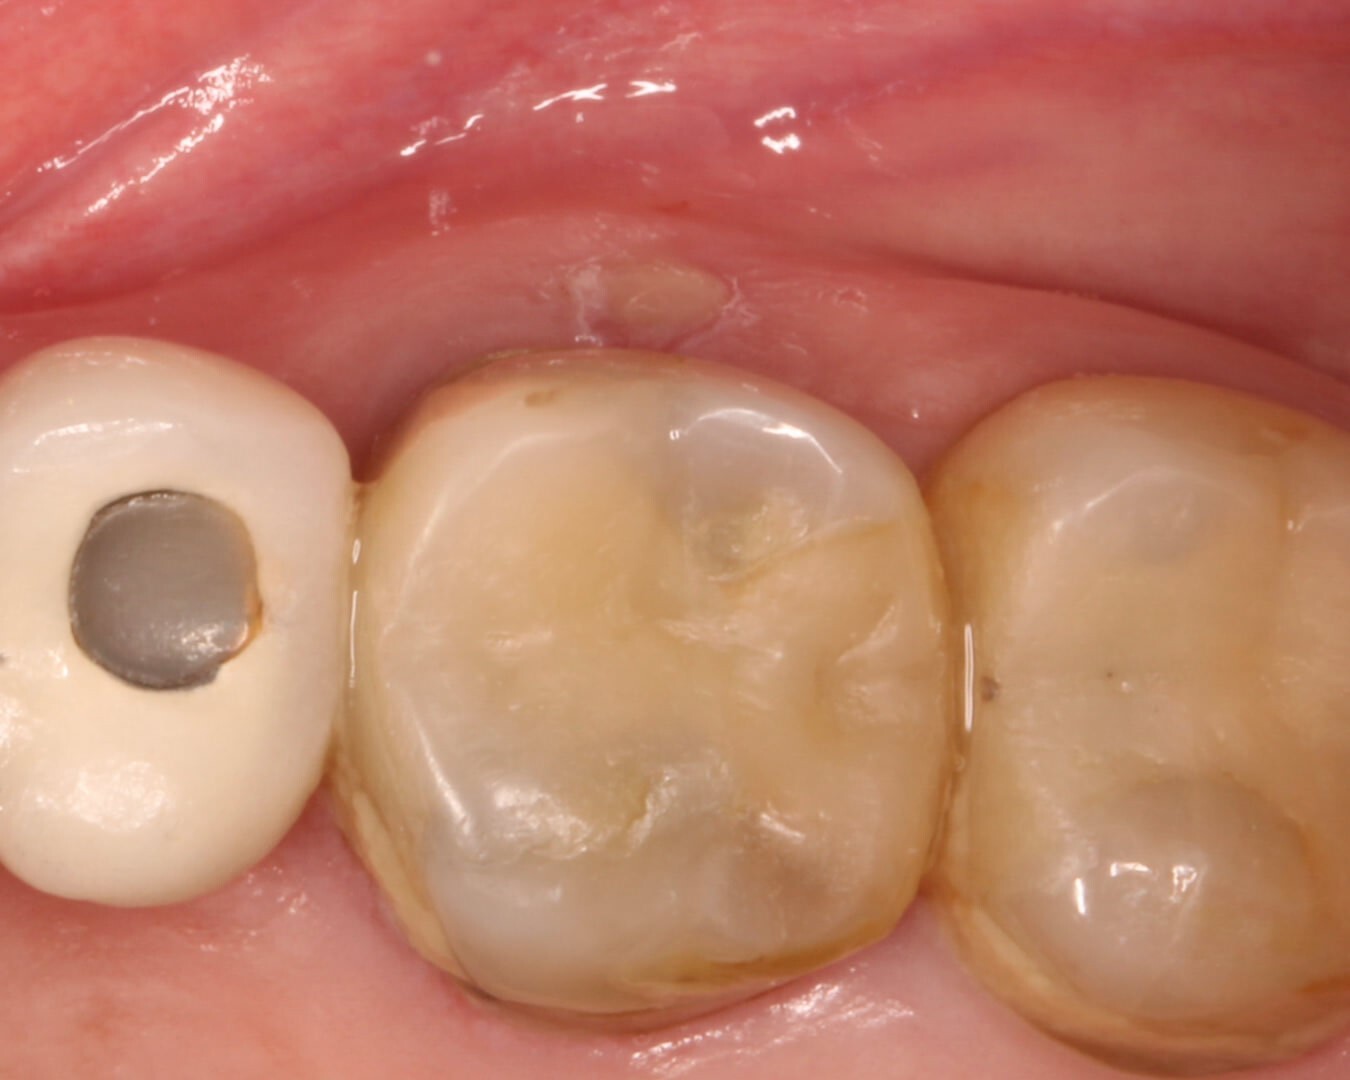

3. By the two-week recall visit, complete closure of the sinus tract was observed, demonstrating favorable resolution of the periradicular inflammation. (Image 6)

4. By the two-week recall visit, complete closure of the sinus tract was observed, demonstrating favorable resolution of the periradicular inflammation. (Image 7,8)